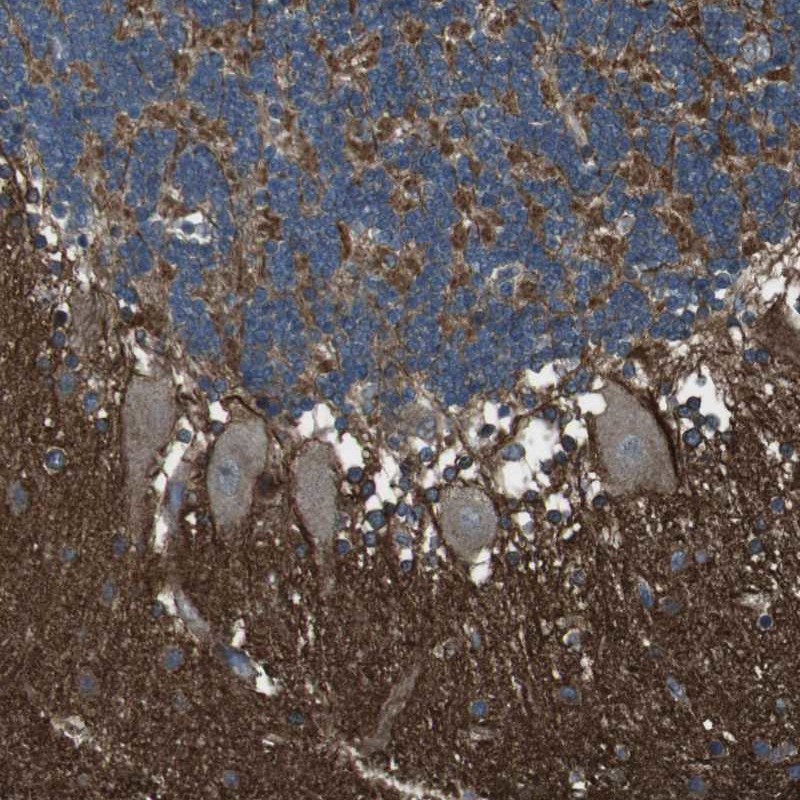

Immunohistochemical staining of human cerebellum shows strong positivity in neuropil.